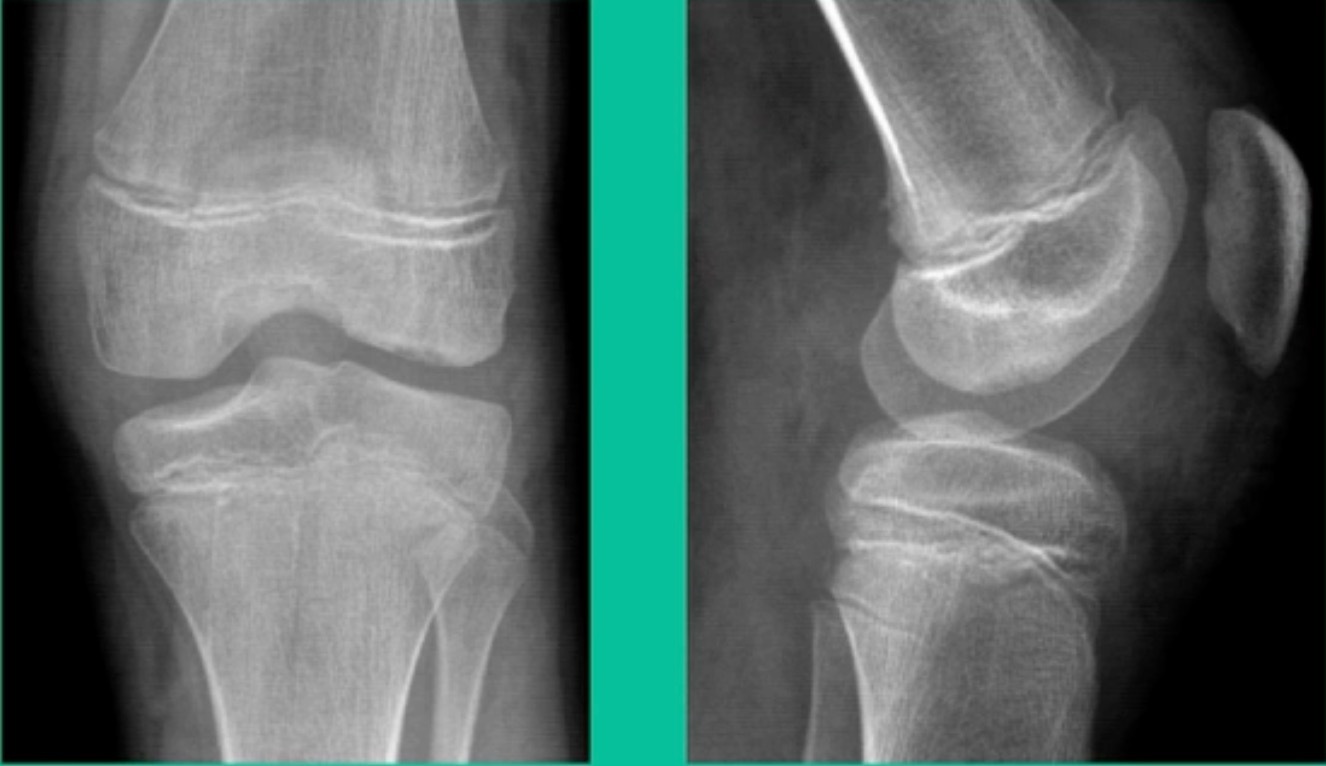

Now, we’ll shift to the adult. This is a 27-year-old. Right knee swelling, activity-related, and classic failed nonsurgical treatment on the lateral side of the knee.

This will probably be fixed. It’s a big piece and we’ll try to preserve it. The literature shows that preservation does pretty well. In this instance, there’s very little bone. It’s somewhat dystrophic, not very encouraging in my mind.

We removed it, and you say, “Well, this is terrible.” Lateral side, how is he going to do? Interestingly, the natural history does not suggest that that person will do badly. Probably the worst ones are going to be the ones who fall off to the side into the trochlea and lateral meniscus.

This is an 18-year-old with a lateral femoral condyle OCD:

Worsening over the last two years, has effusions but no locking, and has a large area of involvement that appears unstable. This is the classic fixation. If you can do this, this is the holy grail. Remember, fracture non-union: you elevate it, debride the base, get rid of any unstable fragments, just take them out, and preserve the major fragment. I’ll use a microfracture awl, but most commonly now I’ll use a pick or a pin, and I’ll drill it. I use two to three metal screws. I bury their heads, and then I come back at eight weeks after being non-weight-bearing, and pull the screws out.